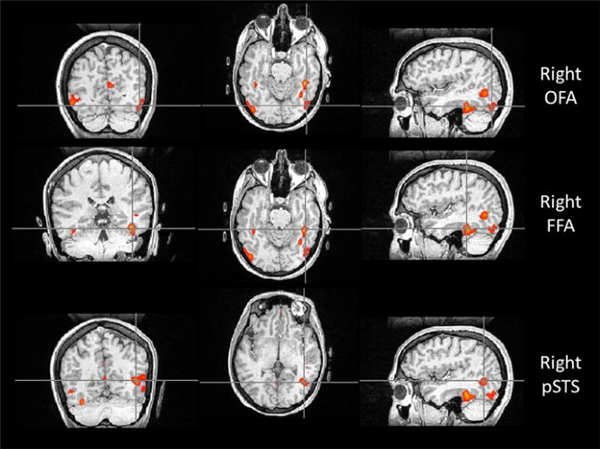

比如,位于枕叶的枕叶面孔区(Occipital Face Area, OFA),就像识脸网络的“先锋部队”。它专门处理眼睛、鼻子和嘴巴等五官“零部件”。当一张脸出现在我们眼前时,OFA 只需 约 100 毫秒 就能被激活,迅速对局部特征进行拆解,并将信息传递给 FFA 和上颞沟(Superior Temporal Sulcus, STS)。所以如果 OFA 出现问题,识别人脸就会变的很困难。

与认脸有关的三个核心脑区,自上而下依次为:OFA(枕叶面孔区)、FFA(梭状回面孔区),以及 STS(上颞沟)。图片来源:doi: 10.1007/s00221-011-2579-1